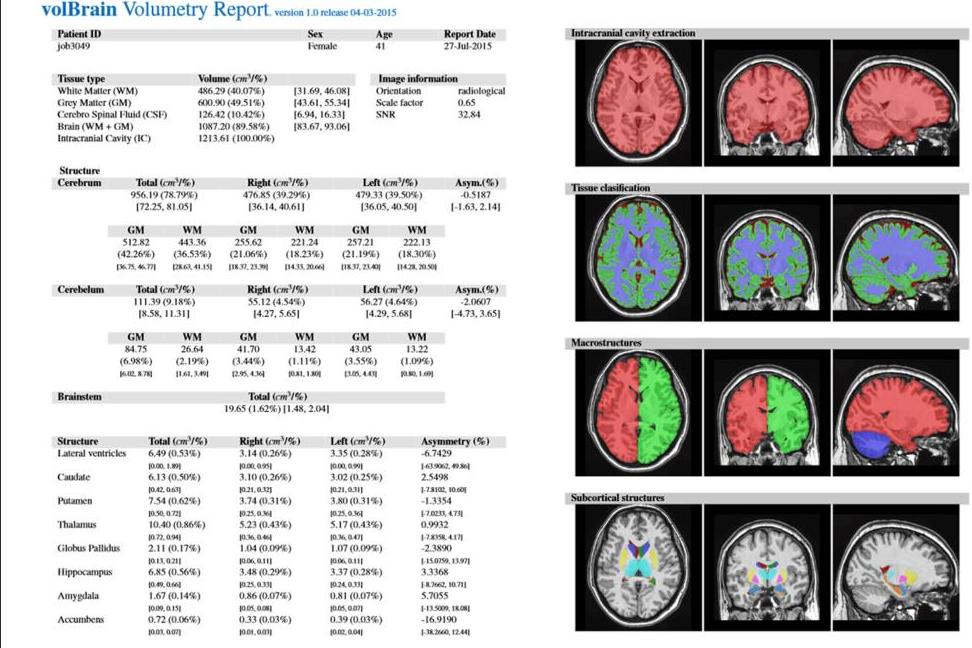

Госзадание «Разработка новой технологии диагностики нейродегенерации и количественной оценки нейропластичности при прогрессирующих типах рассеянного склероза с использованием биомаркеров на основе исследования морфометрических параметров мозга и коннектома»

Результаты: Получены данные об изменении морфометрических данных у пациентов с прогрессирующим типом течения рассеянного склероза в виде снижения объема белого вещества головного мозга, а также белого вещества мозжечка относительно возрастной нормы, с компенсаторным увеличением объема ликворных пространств по конвекситальной поверхности, увеличением объема III и боковых желудочков (в cм3/%). Также отмечалось снижение абсолютного объема субкортикальных структур (таламус, бледный шар, диэнцефалон) относительно возрастной нормы.

Все данные пациента сравниваются с данными здоровых людей, взятых из библиотеки набора данных открытого доступа IXI (Подробнее).

| Графическое представление результатов МР-морфометри |